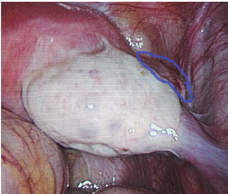

患者,32岁,因"停经2月余,下腹隐痛1 d"于2017.03.02入院。末次月经2016.12.23,入院当日出现下腹隐痛,无阴道流血,无肛门坠胀感,无恶心,无呕吐等不适。既往生育史:0-0-3-0,2015年因右侧输卵管妊娠行腹腔镜下右侧输卵管切除术。妇科检查:外阴已婚式;阴道畅;宫颈轻度糜烂,举痛不明显;宫体前位,饱满,无压痛;右侧附件压痛,未及明显包块,左侧附件未及压痛,未及包块。2017.03.02查血hCG为14 621.28 IU/L,孕酮为21.30 nmol/L。阴道B超结果提示:紧贴子宫右侧角混合性占位27 mm×26 mm×25 mm,边界模糊,内见无回声区17 mm×17 mm×14 mm,2017.03.03行腹腔镜下手术,术中见子宫前位,饱满,左侧附件未见异常,右侧输卵管未见,右侧卵巢3 cm×2 cm×2 cm,致密粘连于右侧宫角,右侧近宫角处的阔韧带上见一直径约3 cm的包块,逐步切开包块,取出绒毛样组织,创面缝合(图3)。术后17 d血hCG下降至正常,恢复好。

腹腔镜技术对诊治异位妊娠优势明显,但我们也应注意规范操作。病例3右侧输卵管切除术后2年,发生重复性异位妊娠,右侧宫角处与卵巢致密粘连,并且发生该处的阔韧带妊娠,可能的原因是前次腹腔镜下输卵管切除术时电凝切除输卵管,剩余输卵管残端过长,且由于腹腔镜能量器械的热量传导作用,从而引起残端缺血坏死所致的局部缺损或薄弱,瘢痕未能完全闭合而形成瘘管。在输卵管残端瘘形成后,异常运行的受精卵则可着床于输卵管残端包埋处的阔韧带内形成阔韧带妊娠。有文献报道,腹膜后妊娠破裂继发的阔韧带妊娠和输卵管间质部妊娠破裂引起的阔韧带的血肿,这可能与阔韧带的解剖结构特点和血运丰富有关[13,14]。相对于剖腹手术,腹腔镜下手术更易发生输卵管残端瘘和阔韧带血肿,从而增加阔韧带妊娠发生概率。根据我院近10年的统计数据显示,各类异位妊娠手术治疗的共6235例,输卵管残端妊娠共有26例,其中17例发生在腹腔镜手术后,这可能是因为剖腹手术,一般采用双重缝合打结法,而腹腔镜手术主要应用的是电凝。因此前次手术时输卵管残端处理得当可大大减少重复性异位妊娠的发生,一定要行输卵管全切,必要时宫角处包埋缝合。